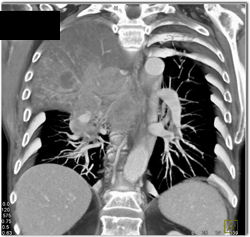

Thickening of Airway Due to Wegener's